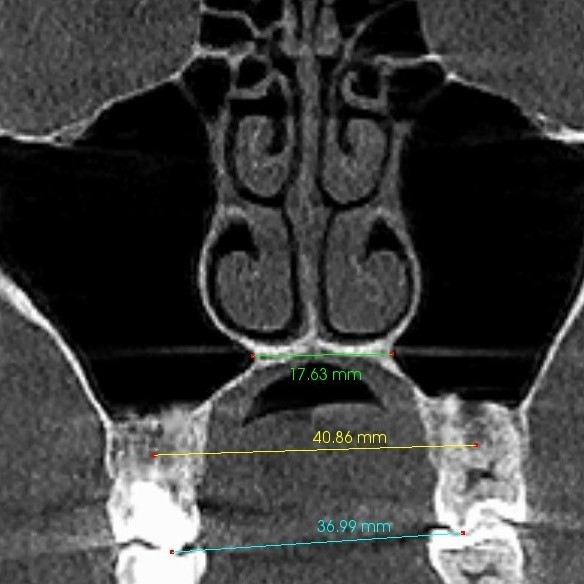

Rzut osiowy podniebienia po ekspansji u osoby dorosłej – widoczne równoległe rozejście się szwu podniebiennego na całej długości: